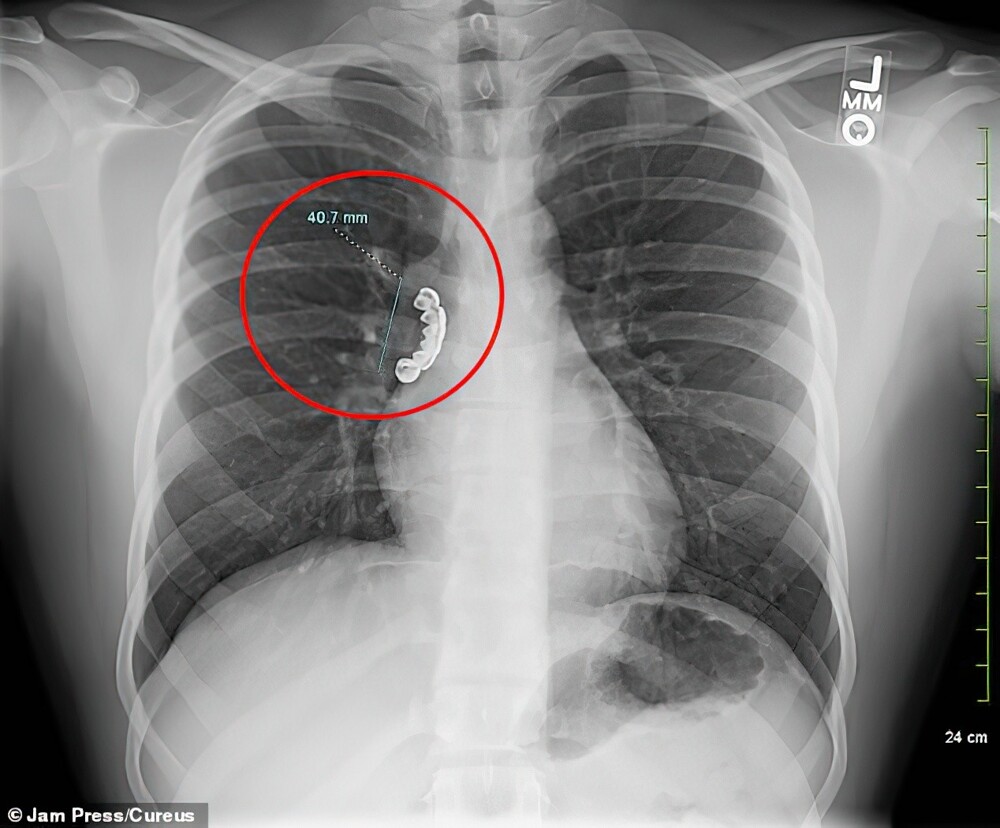

Рентгеновское сканирование показало, что 4-сантиметровая металлическая накладка застряла в правом главном стволовом бронхе, проходившем через легкие.

Врачи срочно отправили пациента на бронхоскопию, чтобы удалить инородный предмет. Эта процедура включает введение тонкой, облегченной трубки, называемой бронхоскопом, в дыхательные пути. Экстренная операция прошла успешно. Парня выписали после процедуры и курса стероидов.